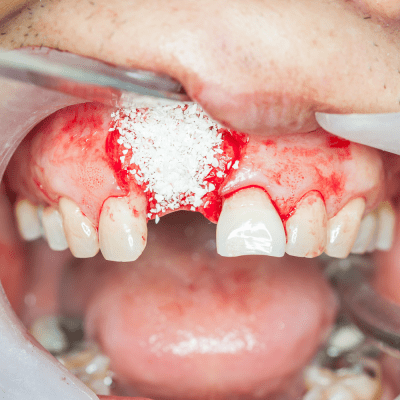

Ghép xương răng nhân tạo sử dụng nguyên liệu là xương được chế tạo từ các chất đảm bảo về mặt an toàn, được cấy ghép vào khoảng thiếu xương răng, giúp tạo điều kiện cho xương tự thân phát triển tốt. Đặc biệt là xương nhân tạo có thể tự tiêu tan sau khi kết thúc vai trò của mình. Xương răng nhân tạo có độ tương thích với toàn bộ bề mặt chung, đem lại cảm giác không bị trống trải.

Nhược điểm: Xương nhân tạo không có độ cứng như xương thật, do đó khi cắn phải đồ cứng ở khu vực cấy ghép xương nhân tạo có khả năng bị bong ra. Đối với một số người, sau khi cấy ghép xương nhân tạo có khả năng sẽ bị tiêu viêm. Tuy nhiên chỉ cần điều trị theo hướng dẫn của bác sĩ sẽ không phải là vấn đề gì to lớn.

Ghép xương nhân tạo đòi hỏi kỹ thuật cao